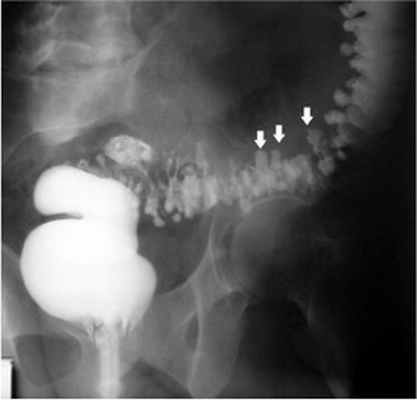

Клинические проявления дивертикулеза толстой кишки и его осложнений не могут служить основанием для установления точного диагноза заболевания. Диагностика и дифференциальная диагностика дивертикулеза толстой кишки основывается на анализе клинических проявлений заболевания и результатах обязательного рентгенологического и эндоскопического исследований толстой кишки.

![Дивертикулез лечение]()

- Ирригоскопия — рентгенологический метод диагностики, при котором в кишечник вводится рентгеноконтрастное вещество на основе солей бария.